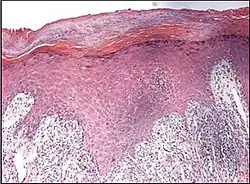

Spongiotic dermatitis

It is characterized by epithelial intercellular edema.[2]